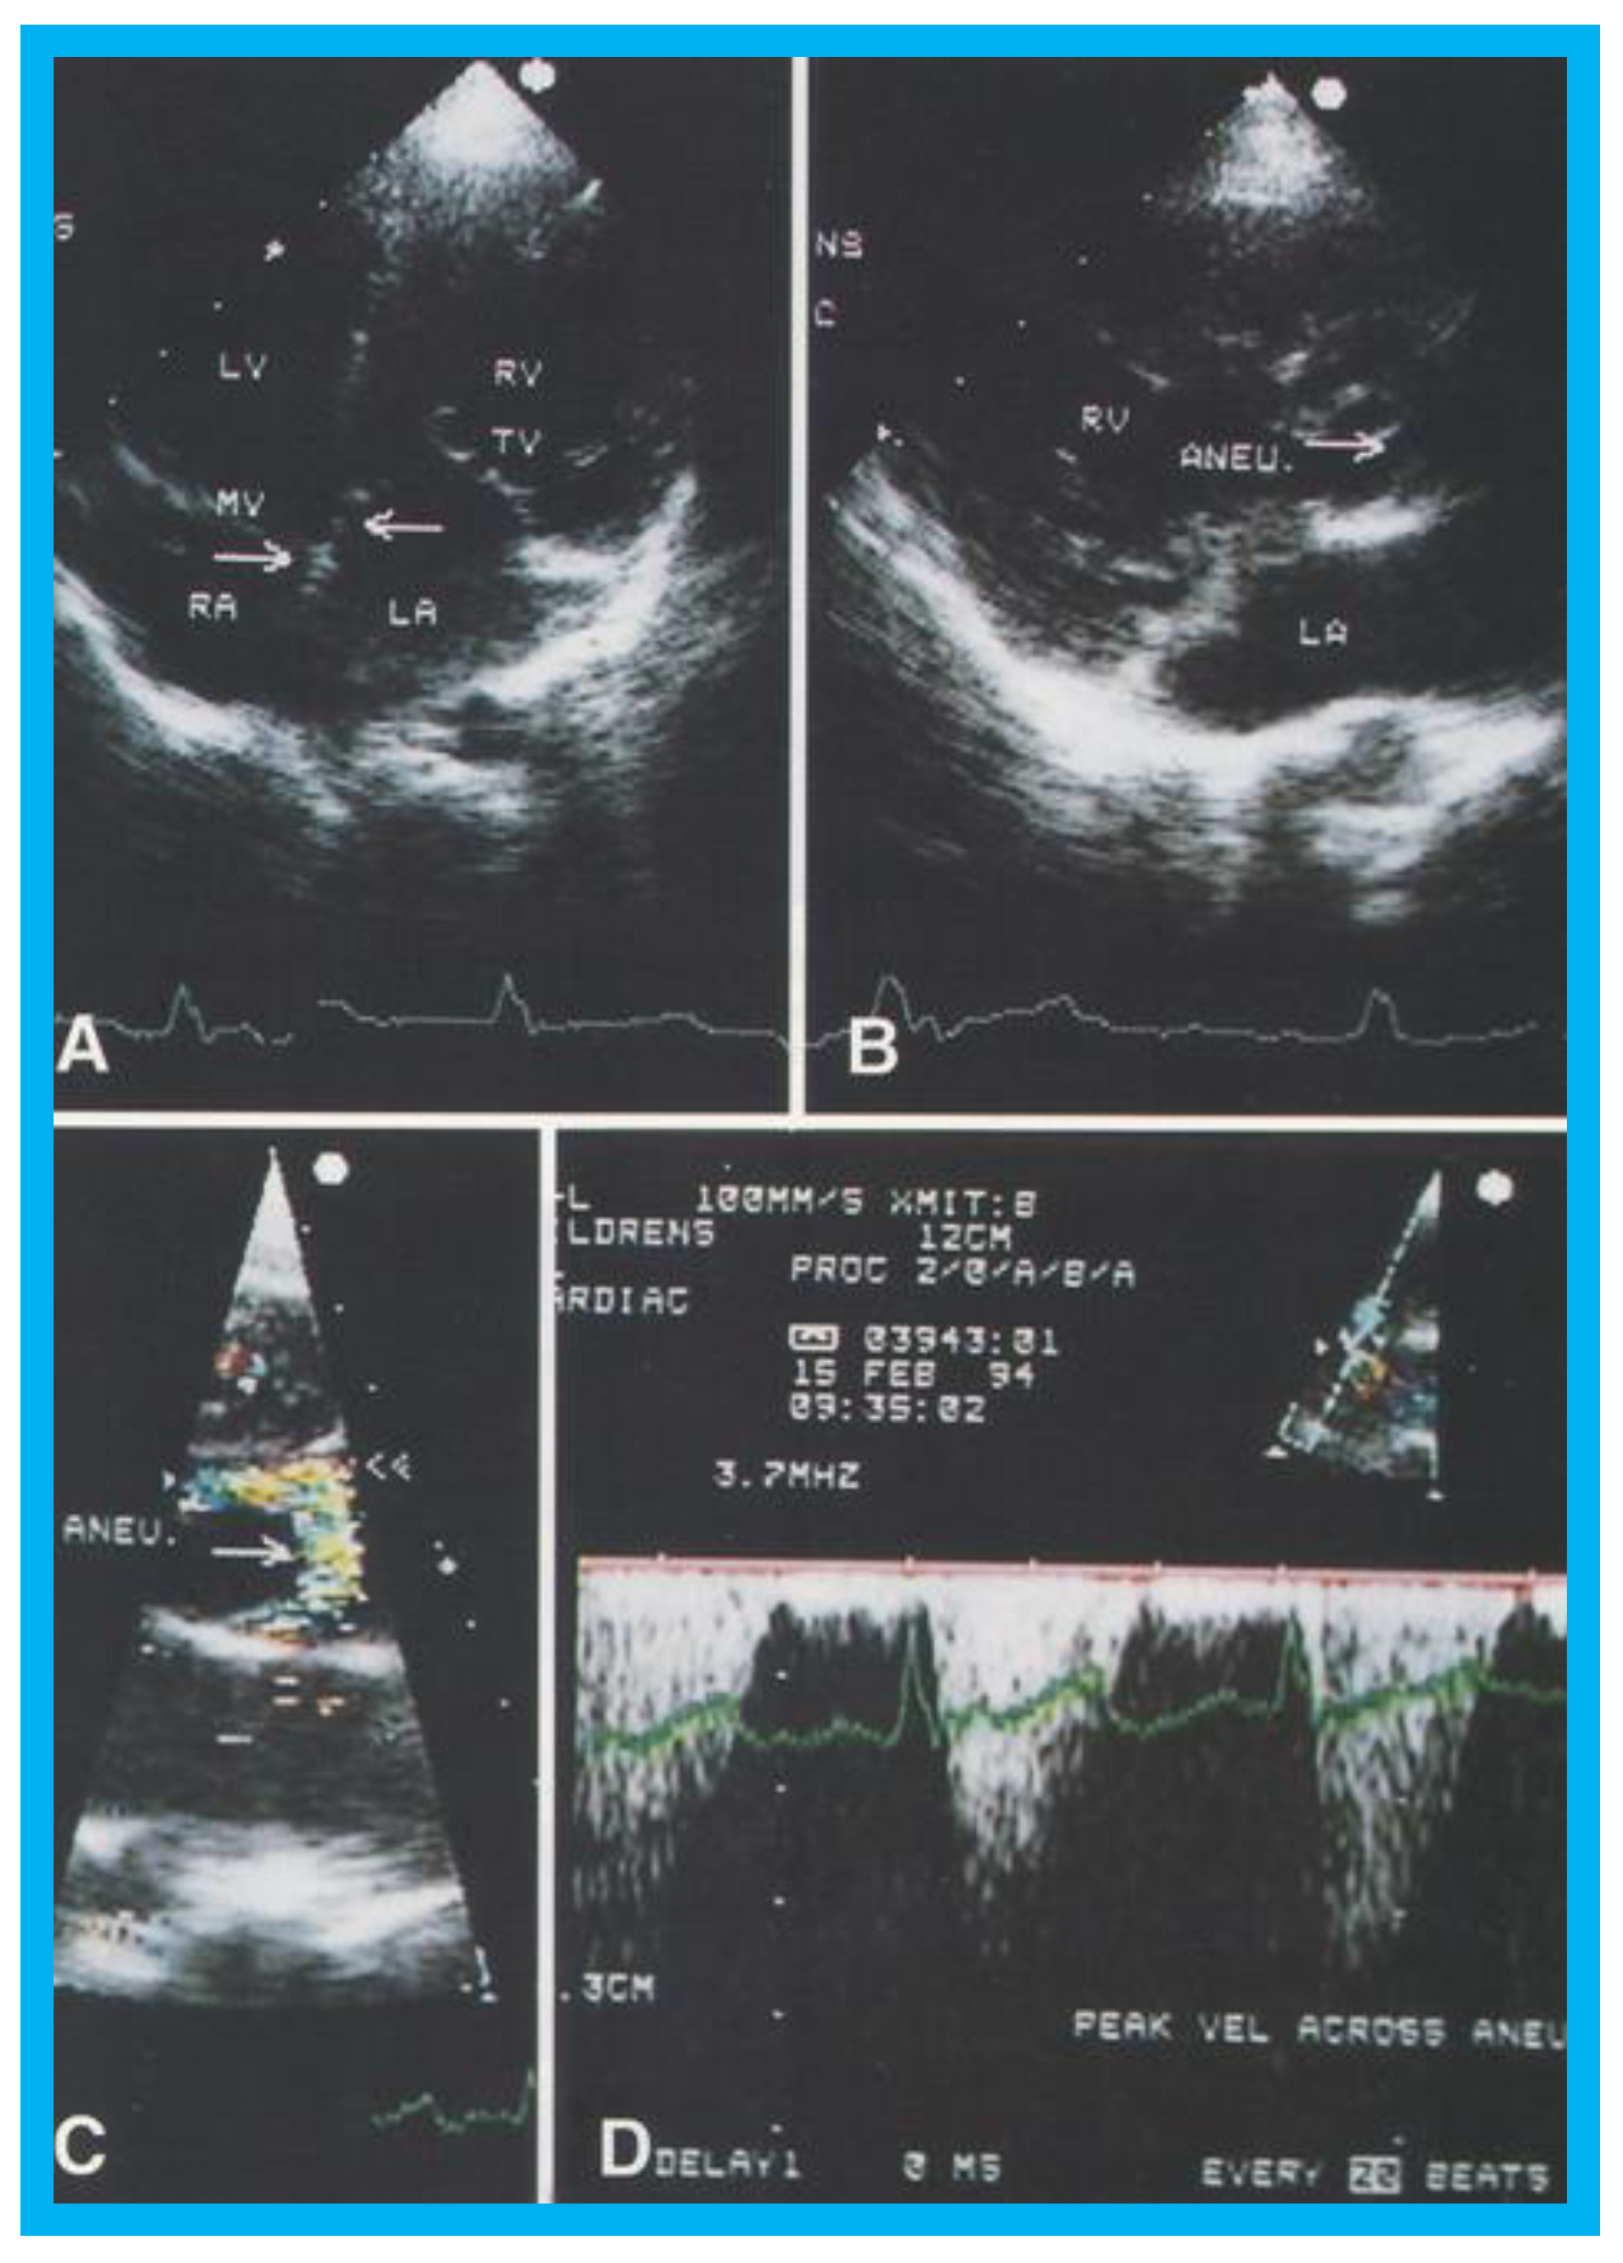

Congenitally corrected transposition of the great arteries (CCTGA) is a rare CHD. The anatomic, physiological, and clinical aspects of CCTGA with particular attention to sub-pulmonary obstruction of the morphologic LV caused by of the membranous ventricular septal aneurysm in patients with both levocardia and dextrocardia [22,23,24] were described in the past. The ventricular morphology and the sub-pulmonary aneurysm were illustrated angiographically elsewhere [22,23,24], and the echo-Doppler features of these anomalies will be demonstrated in Figure 17, Figure 18, Figure 19 and Figure 20.

Figure 17. (A) Selected video frame from apical four chamber projection indicating reversal of the ventricles: The attachment of the mitral valve (MV) leaflet is higher than that of the tricuspid valve (TV), suggesting that the morphologic right ventricle (RV) is on the left side and that the morphologic left ventricle (LV) is on the right side. The right atrium (RA) drains into morphologic LV, and the left atrium (LA) is connected to the morphologic RV. Also note that the medial leaflet of the TV is plastered on to the ventricular septum suggesting Ebstein’s type of morphologic TV. (B,C) Selected video frames from parasternal long axis view demonstrate the aneurysm (Aneu) with color-Doppler turbulence (C). (D) This frame shows a high peak Doppler flow (3.5 m/s), which indicates a peak instantaneous gradient of 49 mmHg. Reproduced from Reddy S.C.B., et al. [22].